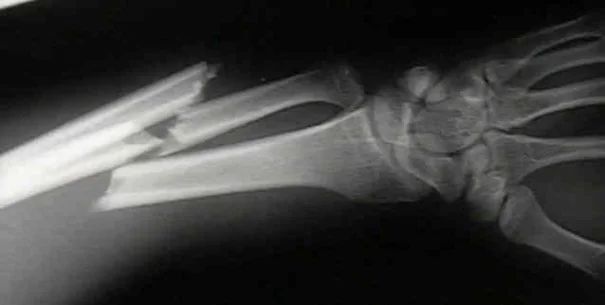

Trauma